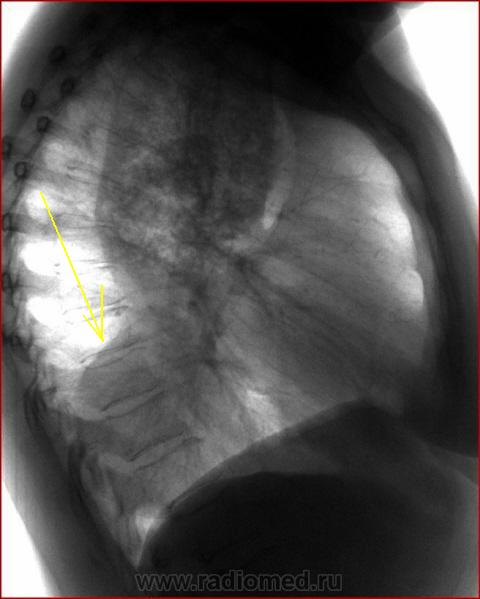

А что это по-Вашему, коллега, что нынче не так часто встречается?

На мой взгляд это может быть и опухолью средостенья, например тератомой, и расширеным пищеводом...

И структуру "образования" можно охарактеризовать, как "отсутствие какой-либо структуры".

Нижняя доля правого лёгкого оттеснена "зажатой" и "отжатой" верхней долей + "объёмное образованием" книзу? Но она нижняя доля сниженной прозрачности - гиповентиляция?

Вы правы - это расширеный пищевод, имеет место ахалазия 4-й степени. Состоит у нас на учете уже года три.